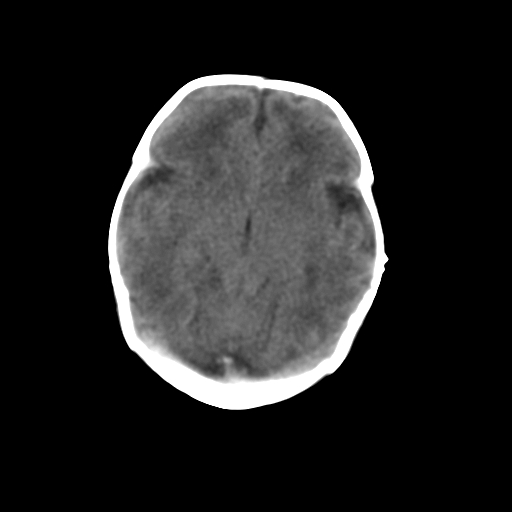

新生儿女2天,有窒息史,经抢救好转!白质最低ct值>23hu,请教各位老师:是否有出血?是否合并缺氧脑病?谢谢!

hie、蛛网膜下腔出血,皮下血舯。

双侧额叶白质低,白质ct值低于18hu可以考虑水肿改变

后纵裂密度高,前纵裂密度低,比较来说应该考虑有蛛网膜下腔出血